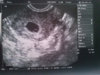

Jak mówi, że jest ok, to jest ok, a w internecie poopisywane są same skrajne przypadki, które zdarzają się raz na może kilka tysięcy ciąż. Także nie martw się, myślę, że wszystko jest w porządku ;-) Na moje oko to USG jest ok